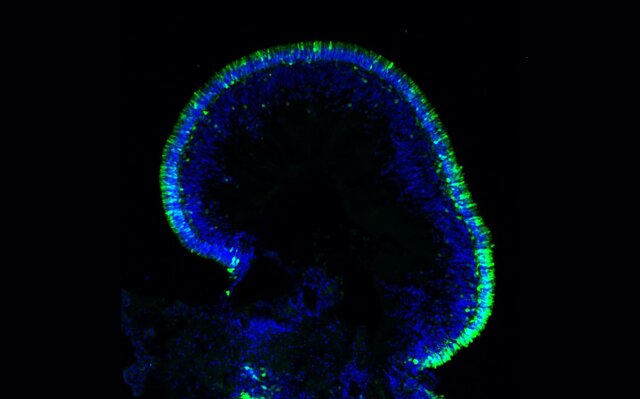

این سلولهای مغزی مشتق شده از سلولهای بنیادی پرتوان القایی(iPSCs)

خود را به شکل ساختارهایی سازماندهی میکنند که وقتی در شرایط خاص رشد

کنند شبیه به بخشهایی از مغز انسان میشوند و به محققان این امکان را

میدهند که رشد مغز و بیماریها را در یک محیط کنترلشدهتر مطالعه کنند.

داویود میگوید: ارگانوئیدهای مشتق شده از سلولهای بنیادی پرتوان

القایی خاص بیمار محدودیتهای مدلهای حیوانی را برطرف میکند زیرا اطلاعات

ژنتیکی اهدا کننده را حفظ میکند و امکان تجزیه و تحلیل اثر ژنتیک بر

تولید، تکثیر و تمایز پیشسازهای عصبی به سلولهای گلیال و نورونها را

فراهم میکند.

تحقیقات ارگانوئیدی نشان داد که در اماس، به ویژه در اماس پیشرونده

اولیه(PPMS)، کاهش در رشد سلولی و تعداد سلولهای بنیادی وجود دارد و

همچنین این بیماری با تغییر در انواع سلولهای مغزی تولید شده همراه است.

به نظر میرسید که این تفاوتها با پروتئینی به نام p۲۱ مرتبط باشند.